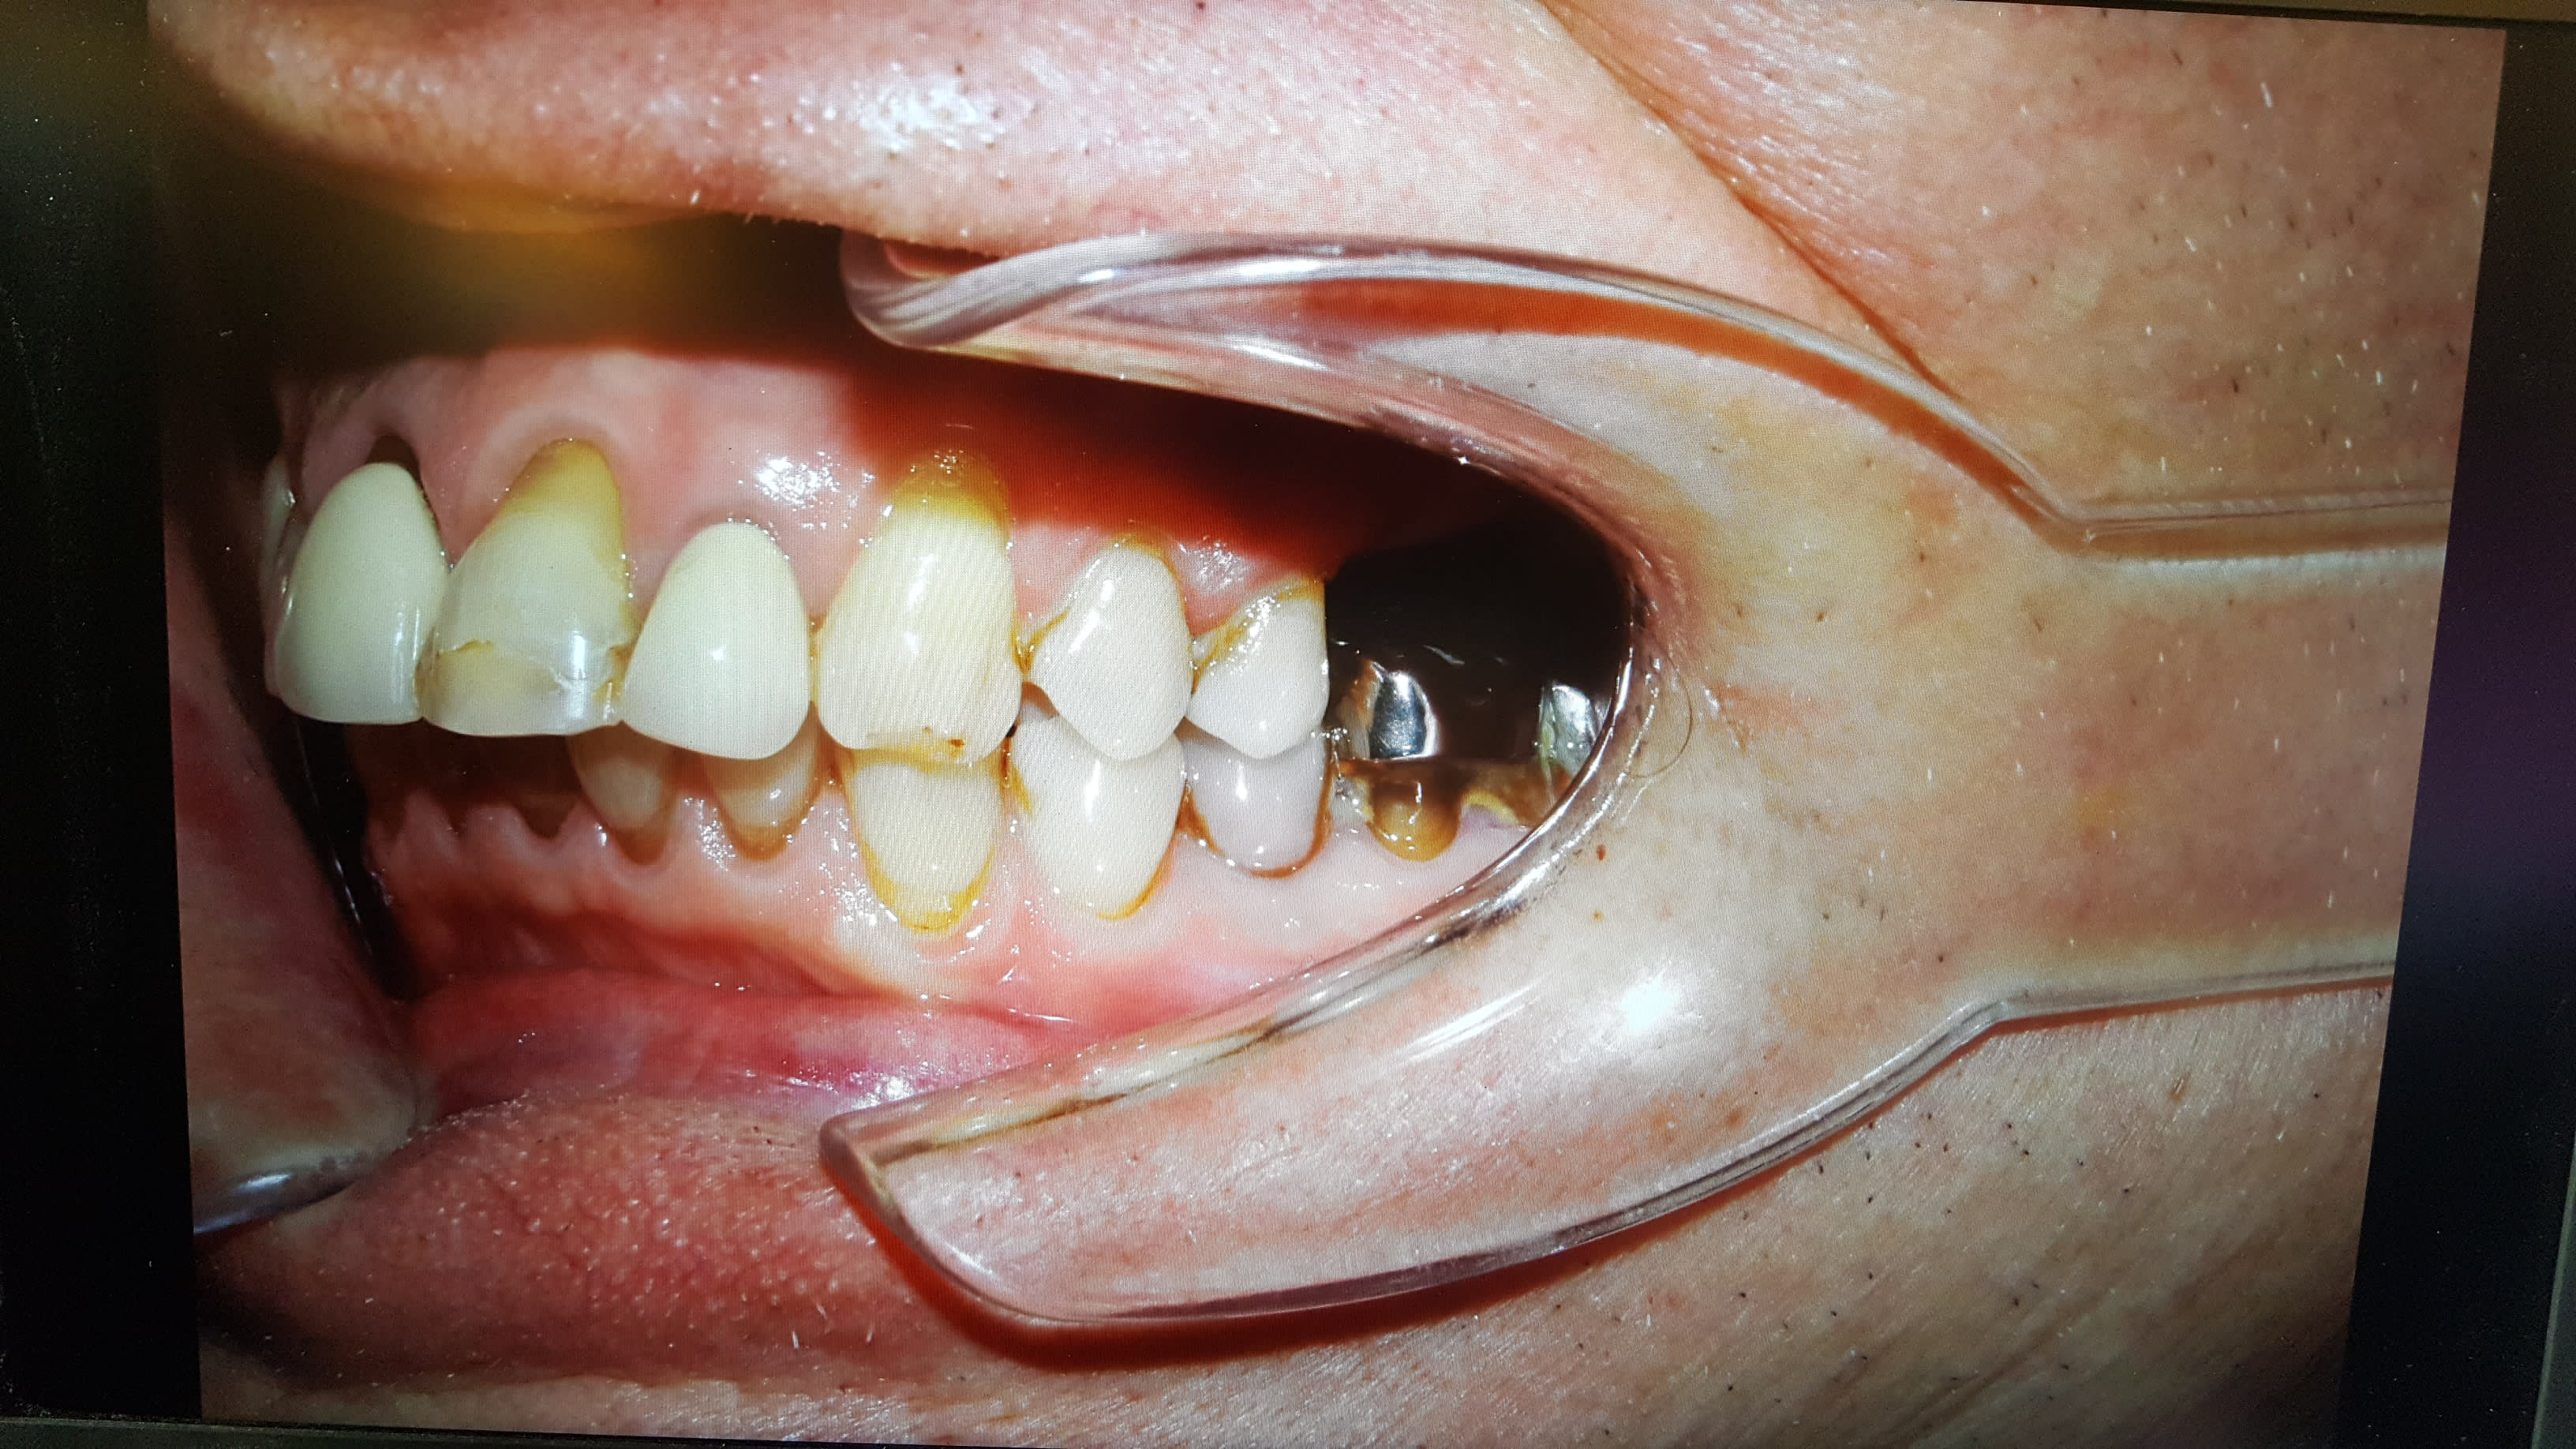

Pour ce qui est des joues : j ai 4 ou 5 types d écarteur différents. Il faut trouver celui bien adapté au patients (En particulier pour l ortho ou la taille des bouches varie tout le temps).

Pour un adulte en omni : pour les secteur latéraux soit les miroir pour des supers photos mais les patients n aiment pas bcp, Soit des ecateurs assez echancrés.